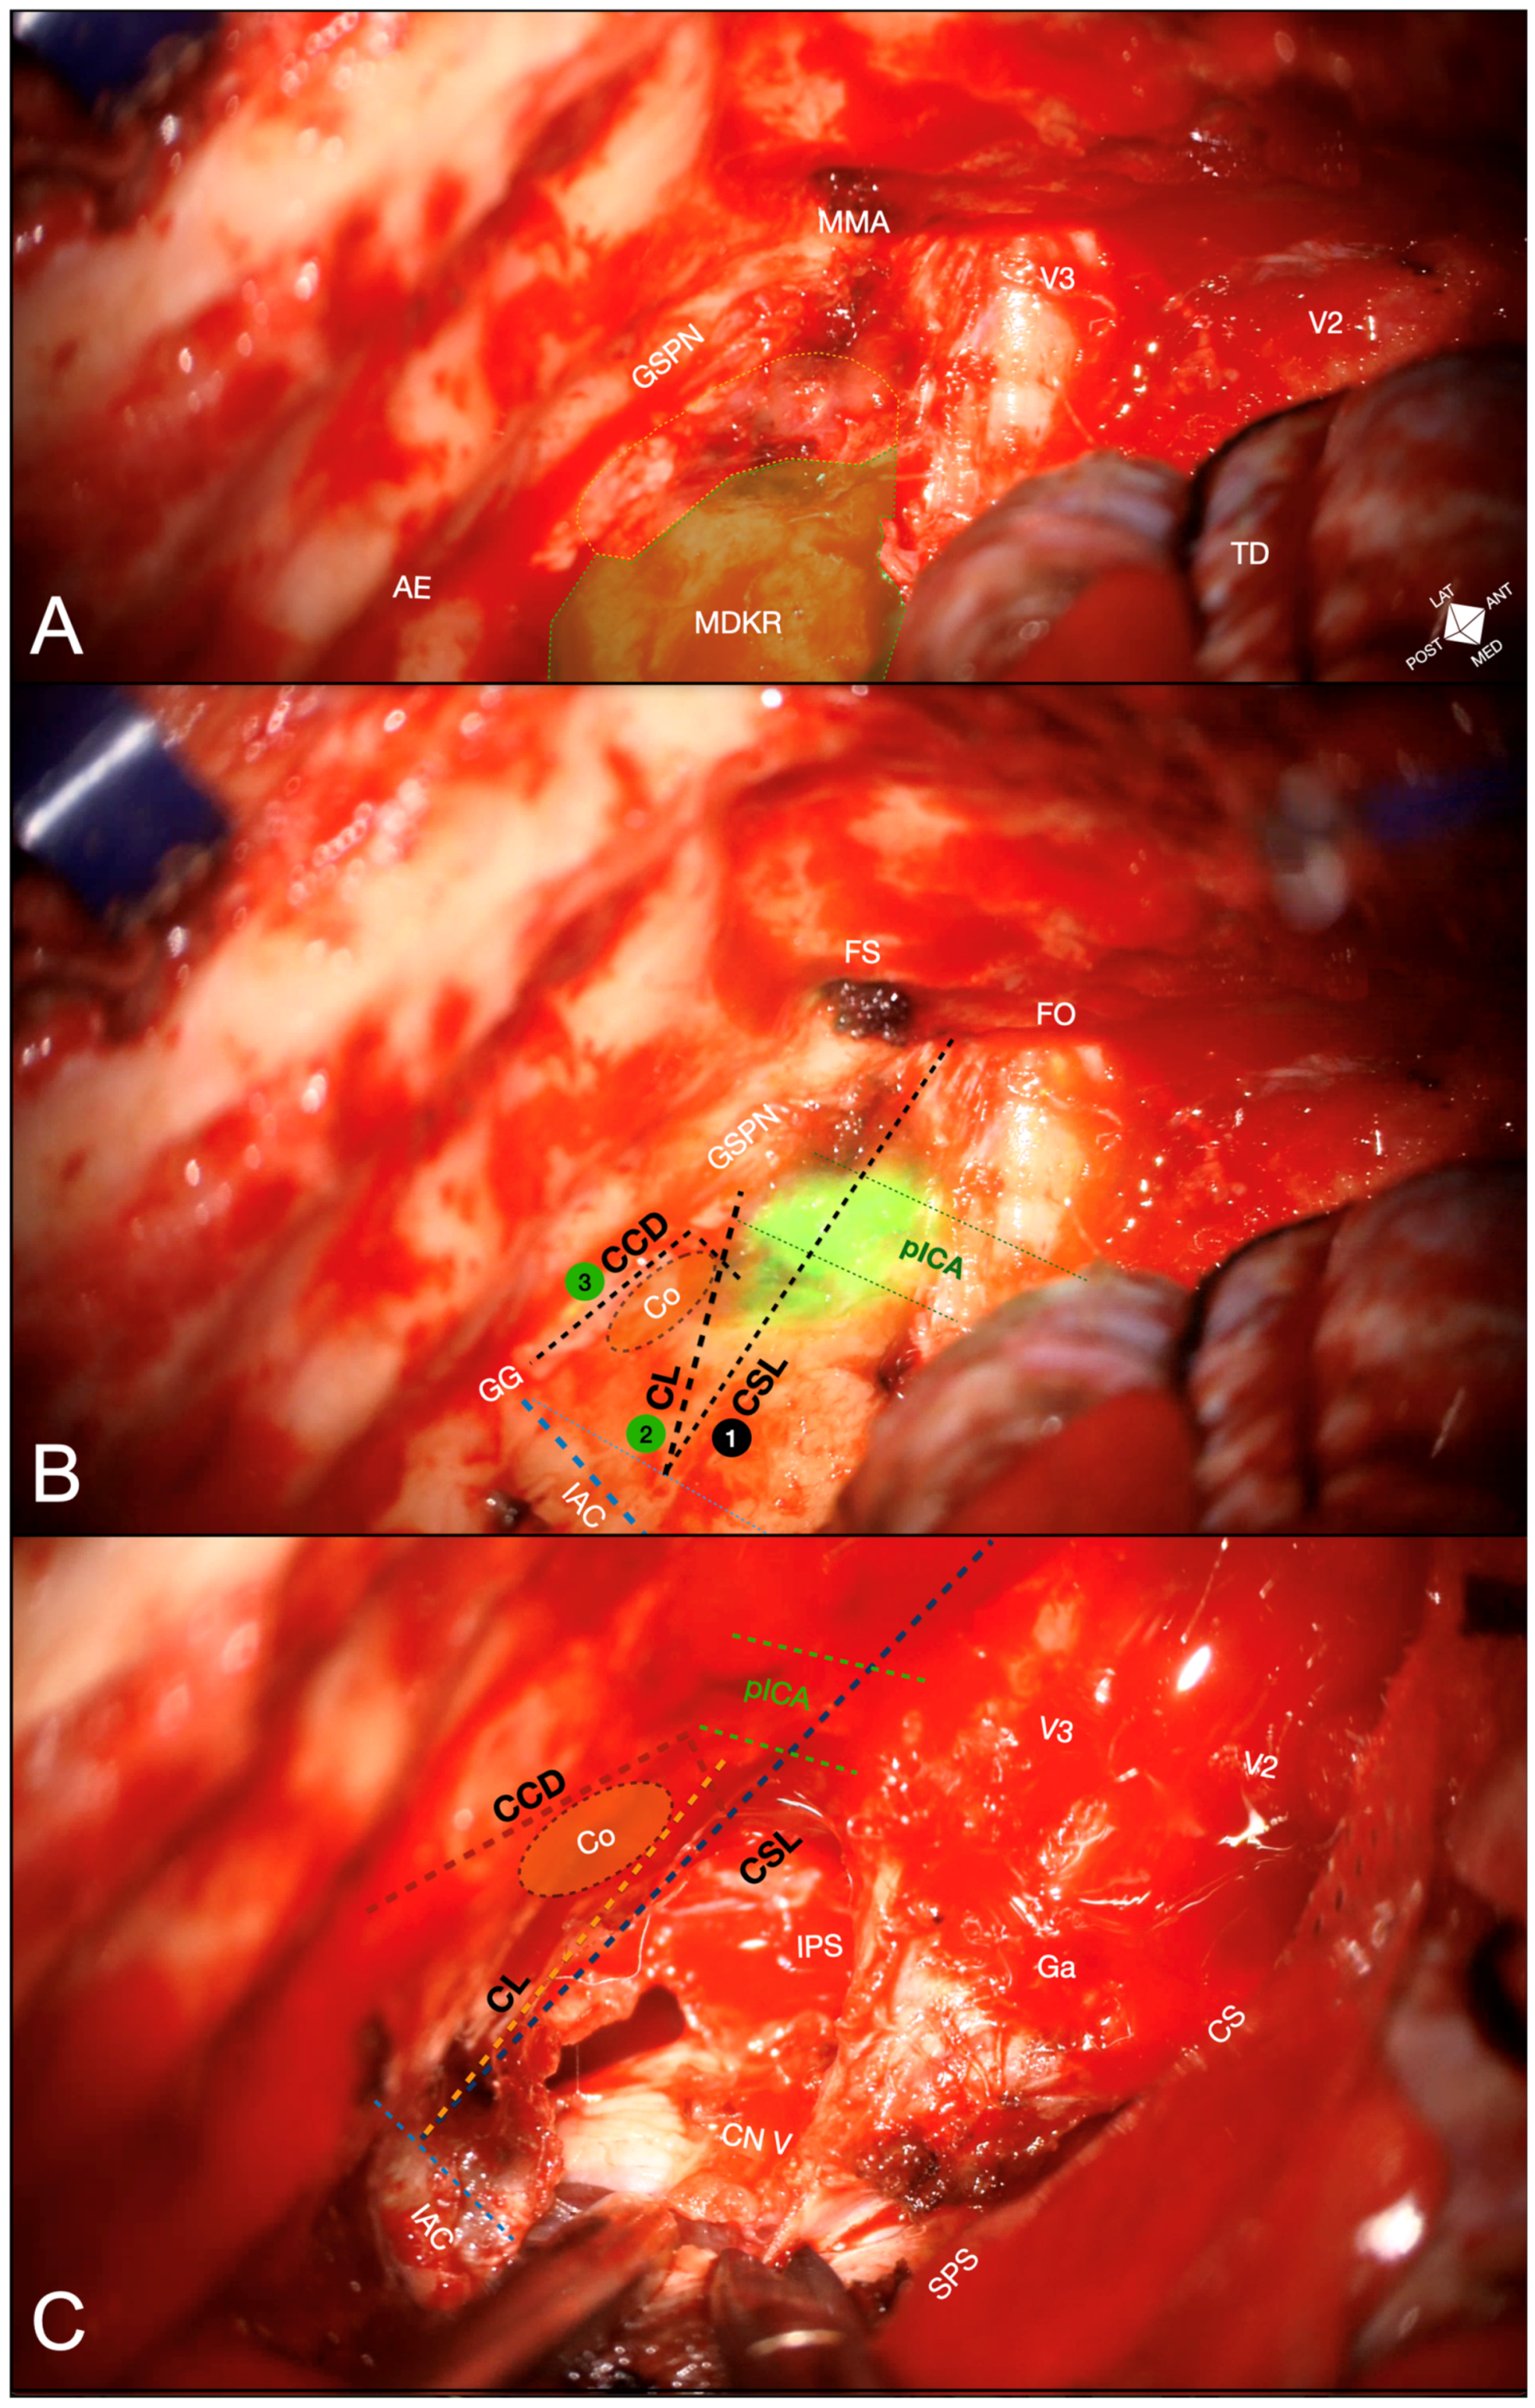

- Cochlear safety line (CSL): Defined as the perpendicular line connecting the lateral rim of the foramen ovale to the transition fold between the roof and anterior wall of the internal acoustic canal (IAC). This line laterally delineates the cochlea [10].

- Petrous ICA (pICA): Identified using intraoperative ICGva.

- Cochlear line (CL): Projected perpendicularly from the petrous ICA–GSPN intersection (measured during ICGva) onto the IAC. This line marks the lateral position of the basal cochlear turn [11].

- Carotido-cochlear distance (CCD): Adapted from Dew et al., measured as the distance between the medial ICA wall (defined with ICGva) and the geniculate ganglion at the fallopian hiatus [12]. Probing through the hiatus or GSPN electrical stimulation with facial nerve EMG confirmation refined this measurement. A 7 mm distance from the geniculate ganglion crotch was designated the safest boundary for identifying the basal cochlear turn [12].